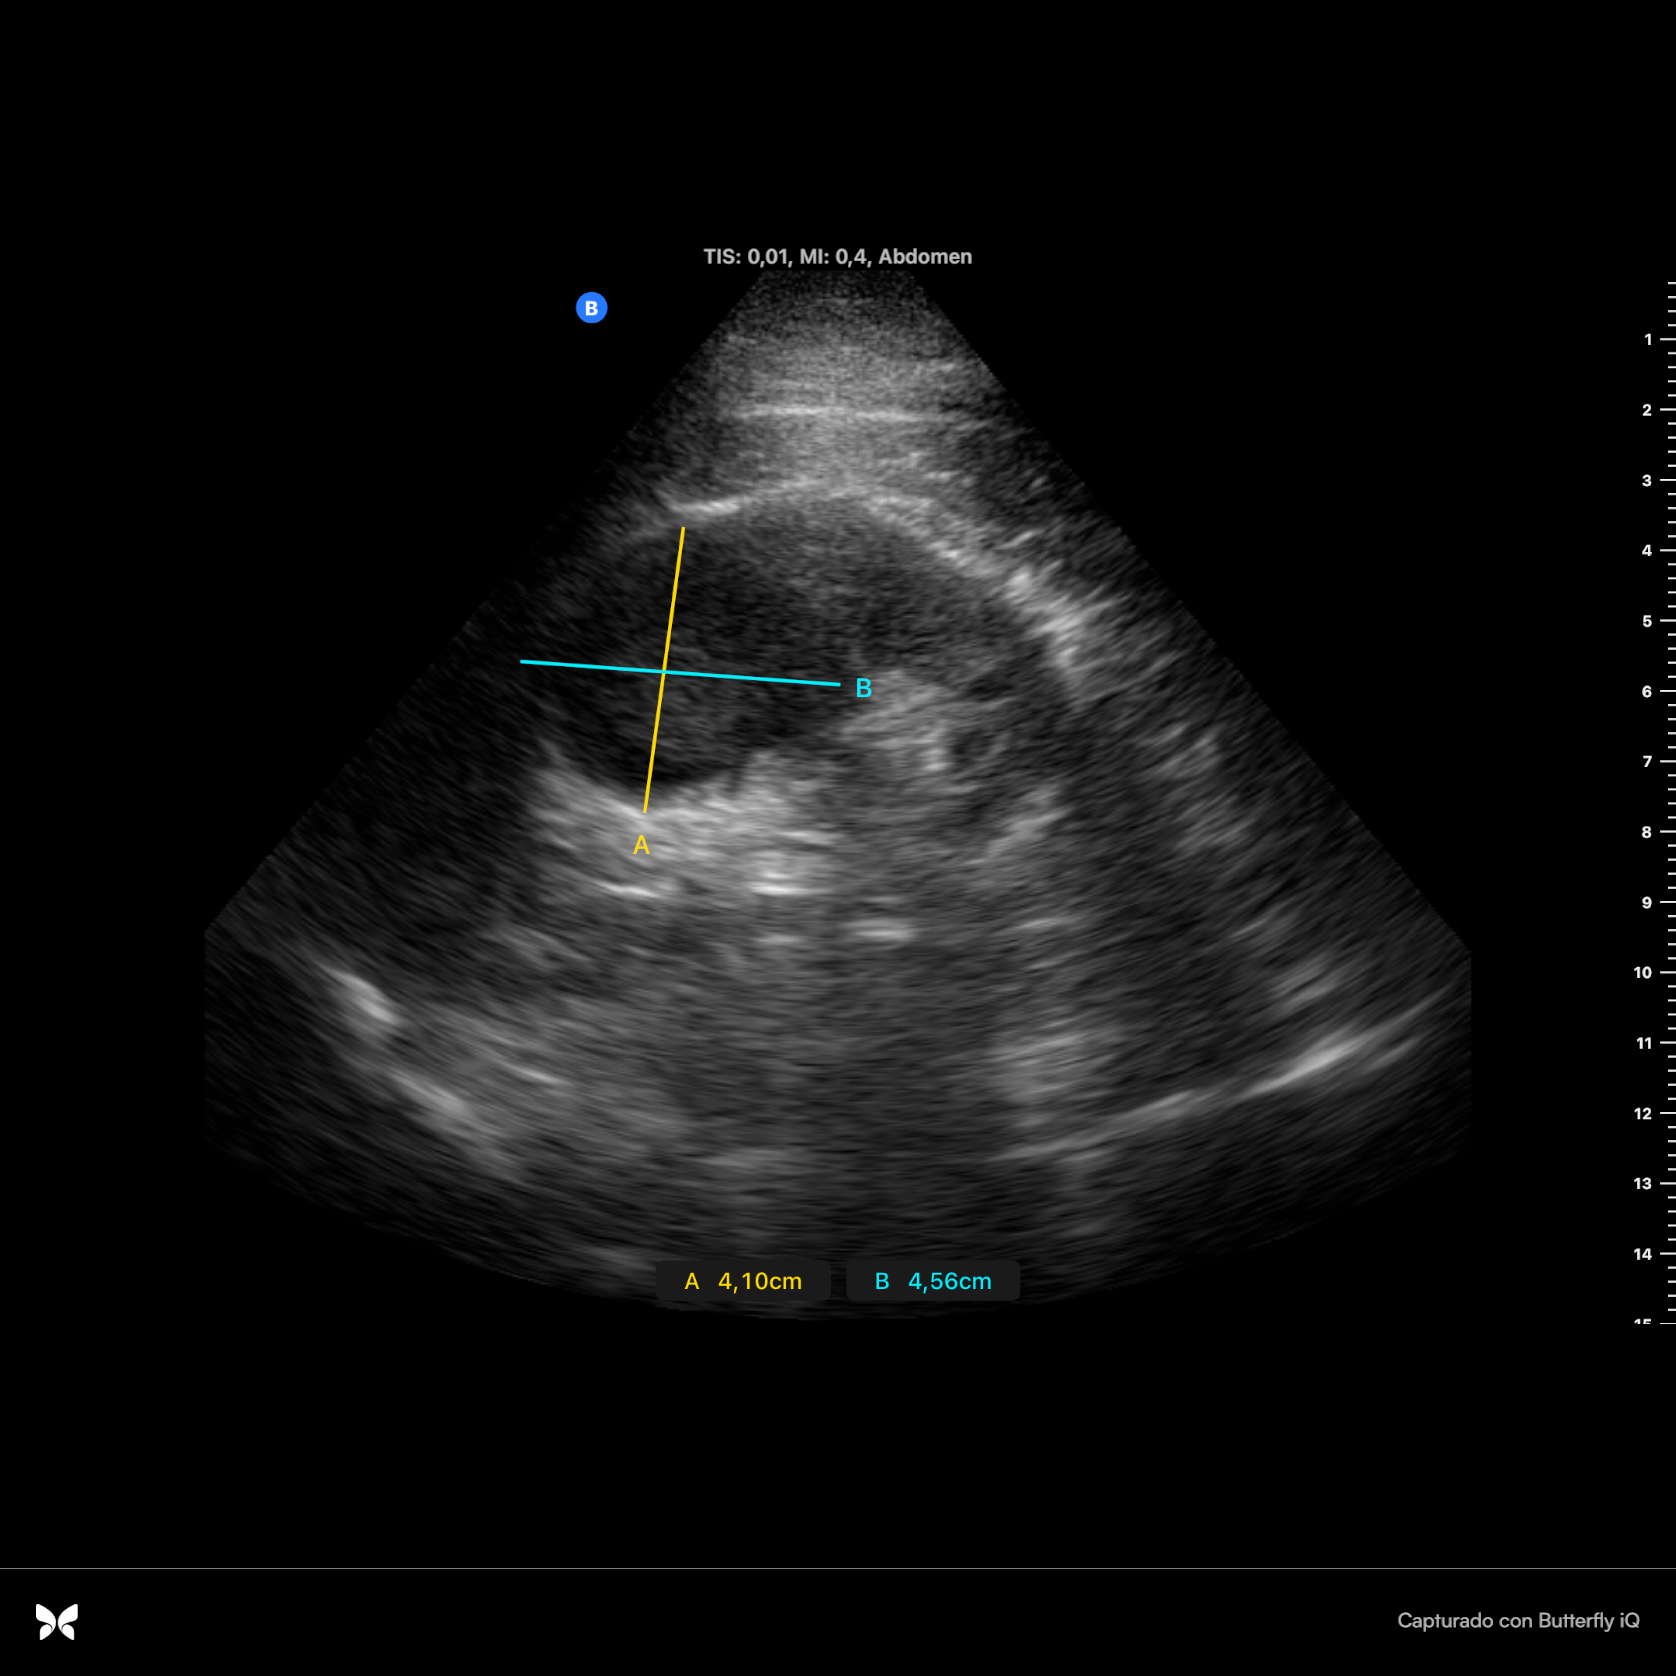

Se realiza con sonda ecográfica portátil. Se inicia el estudio ecográfico del abdomen a nivel de la línea axilar media derecha, donde realizamos cortes longitudinales y transversales. En el riñón derecho se observa, a nivel del polo superior, una lesión sólida heteroecoica, hipoecogénica respecto al parénquima circundante, redondeada, de bordes bien definidos, sin refuerzo posterior (figura 1), de 4,10 x 4,56 cm (figura 2) y con vascularización (Doppler positivo) (figura 3).

• Se solicita tomografía computarizada abdominal de forma preferente, que es informado como masa renal derecha de aproximadamente 41 mm de diámetro, sospechosa de neoplasia renal maligna como 1ª posibilidad, sin evidencia de invasión del espacio perirrenal, afectación ganglionar ni enfermedad a distancia.